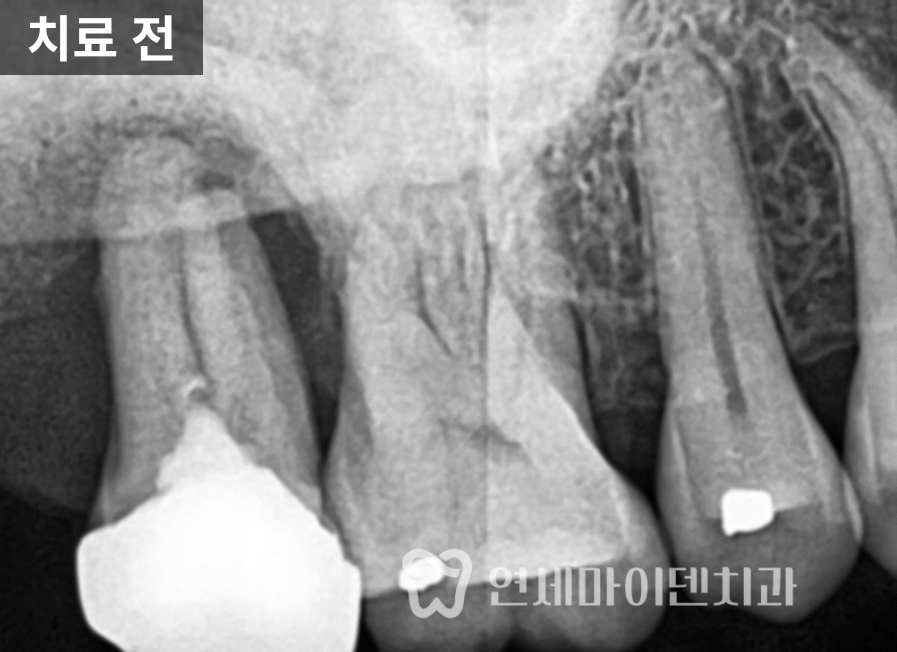

CT를 확인해보니

뼈가 거의 남아 있지 않았고,

손으로도 발치가 가능할 정도였습니다.이 상태를 오래 두면

주변 치아까지 손상될 수 있습니다.임플란트는

✔ 2. 보철 설계 – 맞춤형 지대주

기성 지대주를 사용하는지,

맞춤형 지대주를 사용하는지에 따라

보철의 각도와 형태가 달라집니다.맞춤형 지대주는

주변 치아와의 관계를 고려해

해부학적으로 자연스러운 형태를

만들 수 있습니다.이 부분에서

가격 차이가 발생합니다.